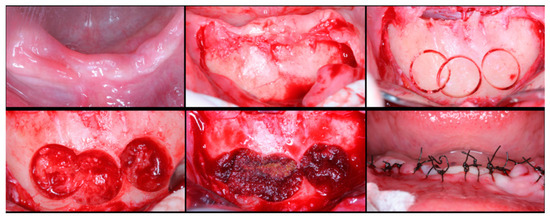

The surgical process, performed by the same surgeon, involved local anesthesia followed by incisions, flap detachment, osteotomy, and membrane elevation. Autologous bone from the mandibular branch (Figure 1) or the mental symphysis (Figure 2), or a porcine xenograft (Figure 3) were used as the graft materials for sinus augmentation. The protocol for this study involved using either two or three syringes of Oteobiol MP3, delivering a volume of approximately 2 to 3 cc per sinus. The contralateral sinus received a similar amount of autologous bone, either from the mental region (desmal with probably some bone of enchondral origin) or the mandibular ramus (desmal origin). Figure 3 and Figure 4 depict one example from each side of maxillary sinus augmentation treatment. Post surgery, the patients followed a prescribed protocol. After six months, a follow-up CT scan was conducted, and dental implants were placed. The final phase involved inserting healing abutments or prostheses, ensuring that no tooth–implant connections were established [20].

Figure 2. Surgical steps for harvesting autologous bone graft from the mental symphysis. In the first row, left to right: anterior mandibular overview, incision and flap detachment, graft drilling. In the second row, left to right: graft removal, chin filling, and sutures.